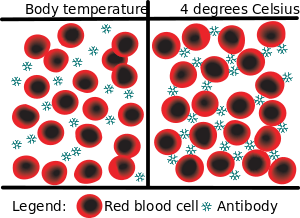

| Cold agglutination - at body temperature, the antibodies do not attach to the red blood cells. At lower temperatures, however, the antibodies react to Ii antigens, bringing the red blood cells together, a process known as agglutination | |

Cold agglutinin disease is an autoimmune disease characterized by the presence of high concentrations of circulating antibodies, usually IgM, directed against red blood cells.[1] It is a form of autoimmune hemolytic anemia, specifically one in which antibodies only bind red blood cells at low body temperatures, typically 28-31 °C.

At body temperatures of 28-31 °C, such as those encountered during winter months, and occasionally at body temperatures of 37 °C, antibodies (generally IgM) bind to the polysaccharide region of glycoproteins on the surface of red blood cells (typically the I antigen, i antigen, and Pr antigens). Binding of antibodies to red blood cells activates the classical pathway of the complement system. If the complement response is sufficient, red blood cells are damaged by the membrane attack complex, an effector of the complement cascade. In the formation of the membrane attack complex, several complement proteins are inserted into the red blood cell membrane, forming pores that lead to membrane instability and intravascular hemolysis (destruction of the red blood cell within the blood vessels).